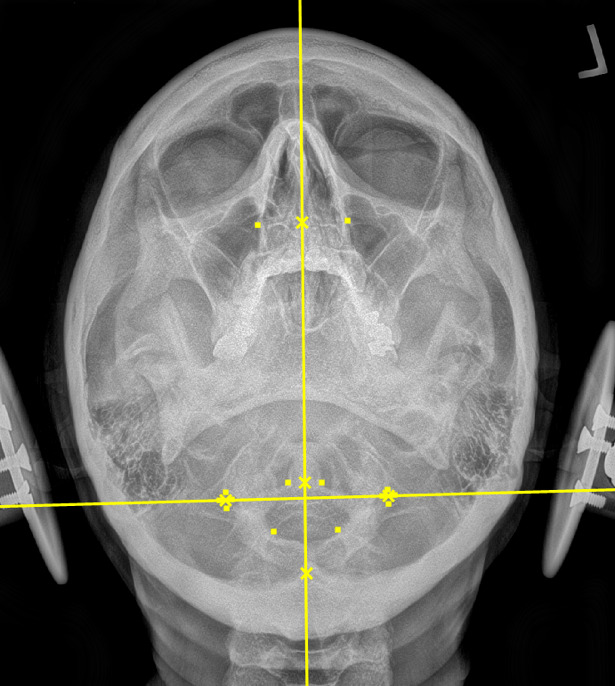

During the initial examination, the chiropractor evaluates the patient’s postural findings, including standing head tilt, head rotation, shoulder height comparison, hip height comparison, lower neck deviation, and supine leg-length inequality. The chiropractor will then take 3 radiographic images of the CCJ minimum to view the alignment in a projected 3-dimension. These images are the cervical neutral lateral (sagittal plane), the nasium (frontal plane), and the vertex (transverse plane). A series of measurements are graphed on the radiographs to assess for alignment. Then, the Orthospinology upper cervical procedure provides a calculation and vectored angle based on these measurements to reduce the misalignment. The chiropractor will use this angle to administer the adjustment to the CCJ. Immediately after the adjustment, the chiropractor evaluates the postural findings for correction. If it has improved, the chiropractor repeats the nasium and vertex views to observe for structural correction. If the postural findings do not improve, the chiropractor may administer a subsequent adjustment before the post-imaging is taken.12